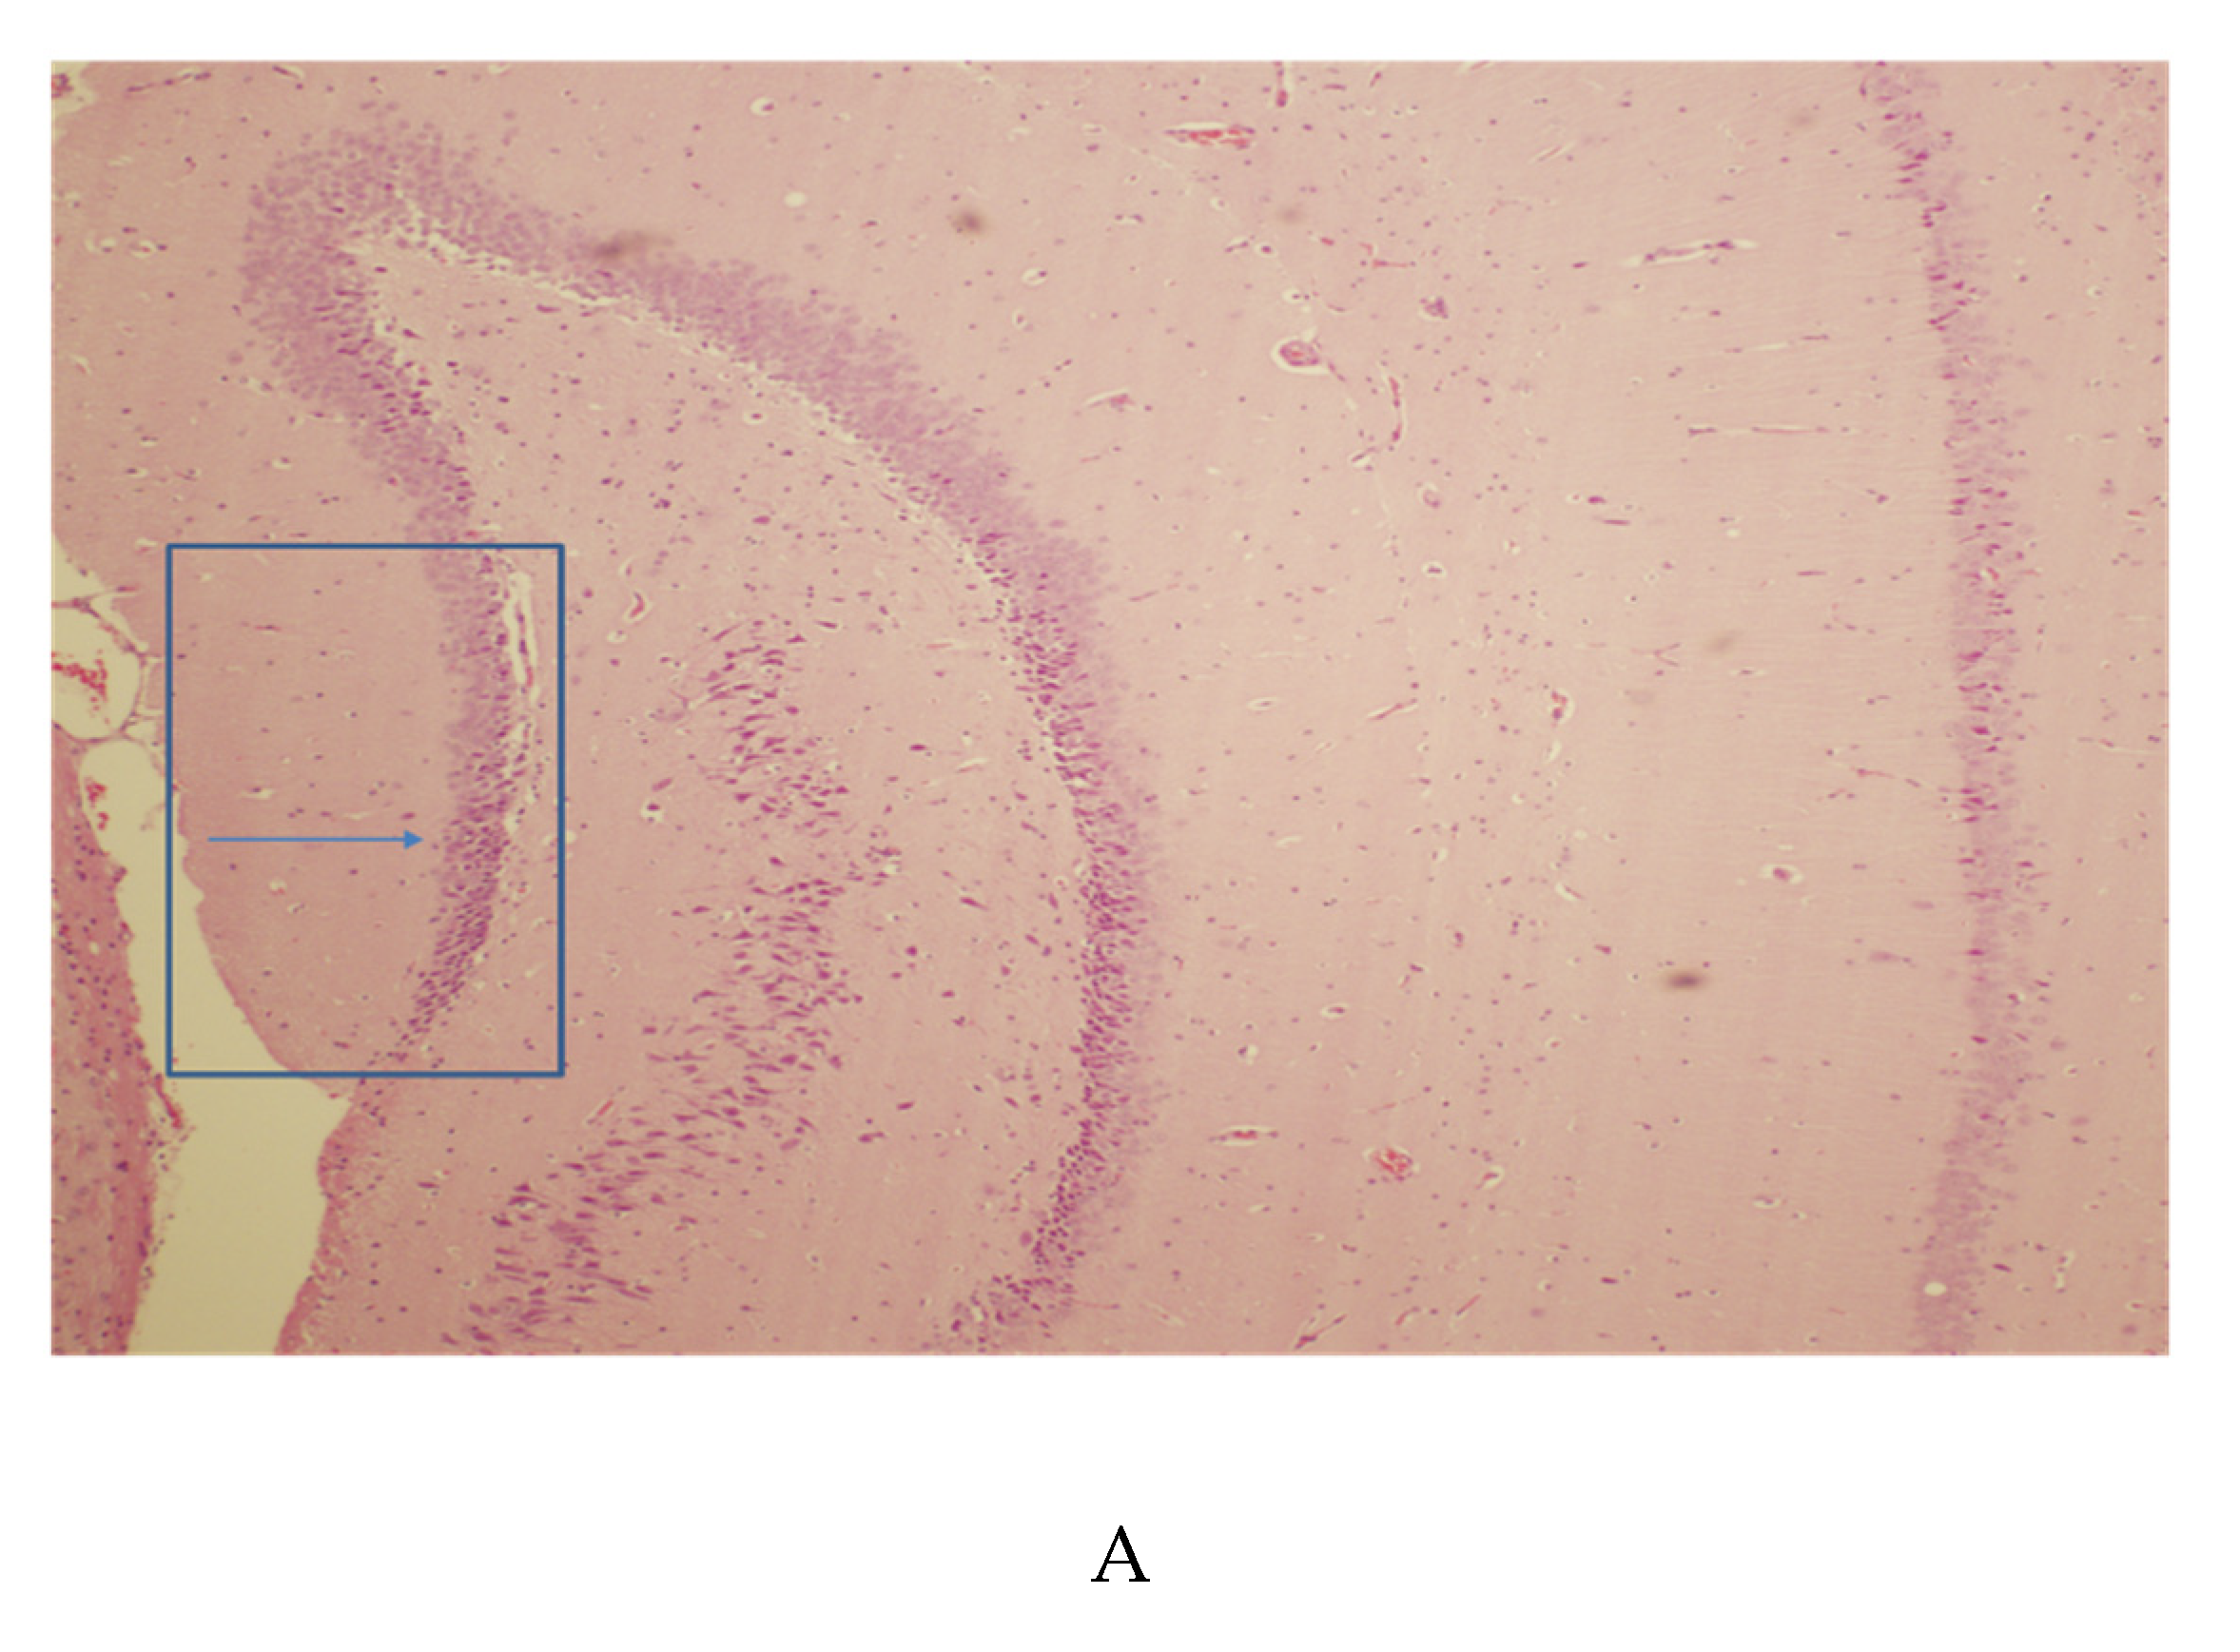

3.2. Hippocampal Pathology

3.3. Striatal Pathology